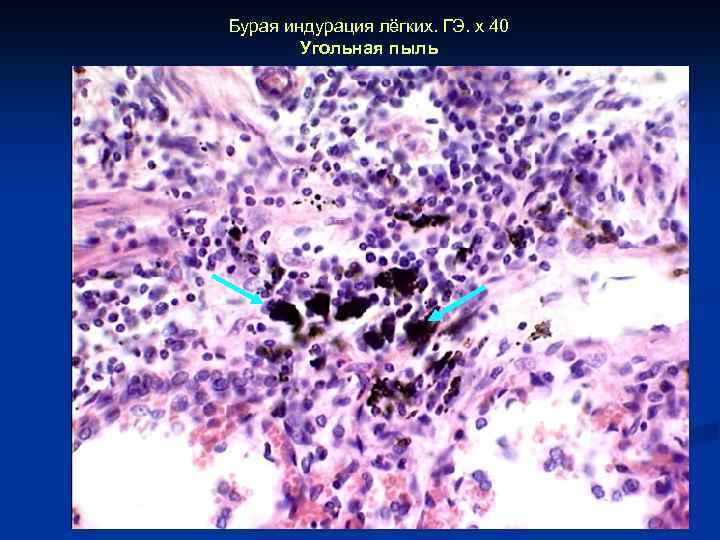

Бурая индурация лёгких. ГЭ. х 40 Угольная пыль